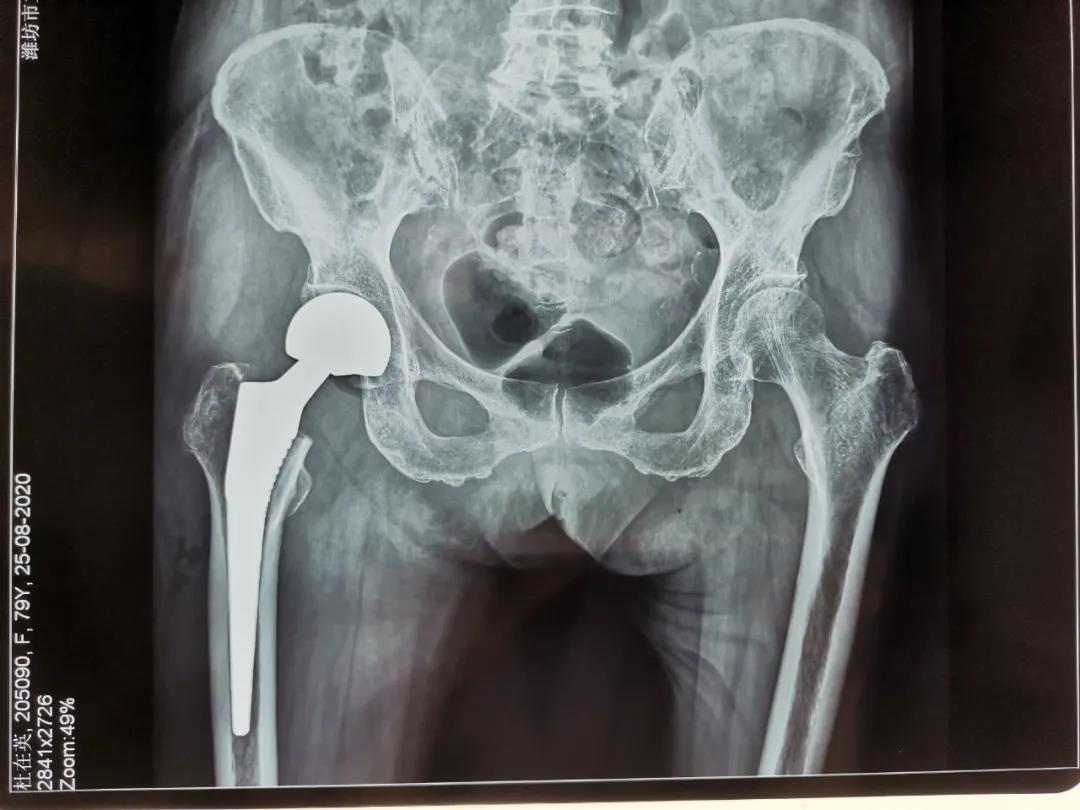

人工股骨頭置換手術(shù)治療老年股骨頸骨折

79歲的杜大娘在家不慎摔倒,跌傷右髖部,許冬雷主任為其主刀行右股骨頸骨折人工股骨頭置換術(shù),用時(shí)短,出血少,患者清醒后就說腿不疼了,術(shù)后第一天見到醫(yī)生就豎大拇指,激動(dòng)地說:“手術(shù)前我很害怕、也很焦慮,沒想到手術(shù)后一點(diǎn)也沒有感覺到疼痛”。術(shù)后第3天就可以下地活動(dòng)了,老人的生活又恢復(fù)了往日的悠然自在。

骨二科采用人工半髖關(guān)節(jié)置換(高齡身體基礎(chǔ)差患者)或人工全髖關(guān)節(jié)置換(相對年輕,身體條件較好患者)能夠迅速恢復(fù)患者的下床行走及生活自理能力,避免長期臥床引起的并發(fā)癥,減輕患者家屬的護(hù)理負(fù)擔(dān),提高患者的生活質(zhì)量,是治療老年股骨頸骨折首選治療方案。